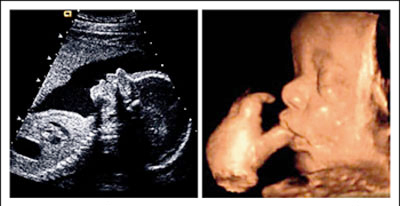

เปรียบเทียบอัลตร้าซาวด์ 2 มิติ และ 4 มิติ ( รูปซ้าย อัลตร้าซาวด์ 2 มิติ / รูปขวา อัลตร้าซาวด์ 4 มิติ )

- 3. สามารถมองเห็นพฤติกรรมต่างๆ ของทารกในครรภ์ได้อย่างชัดเจน ซึ่งการตรวจด้วย อัลตร้าซาวด์แบบ 2 มิติ อาจมองเห็นได้ยาก หรือไม่อาจมองเห็นได้ เช่น สามารถมองเห็นทารกกำลังหาว ดูดนิ้ว ยิ้ม กระพริบตา หรือขยับนิ้วมือ ที่สำคัญยังสร้างความผูกพันในครอบครัวระหว่างพ่อแม่ลูกเริ่มก่อตัวขึ้นตั้งแต่ทารกยังอยู่ในครรภ์